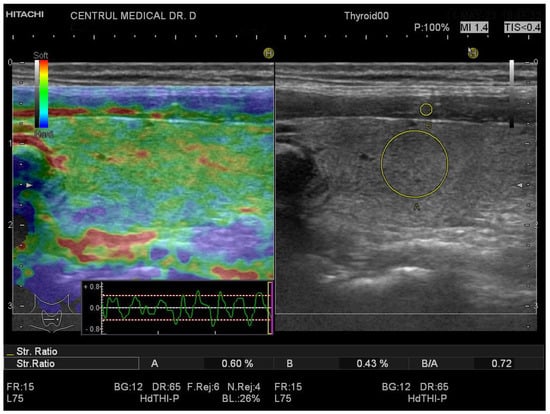

2.4. Conventional Ultrasound and Elastography Examination

3.1. Strain Elastography Measurements

3.2. SWE Measurements